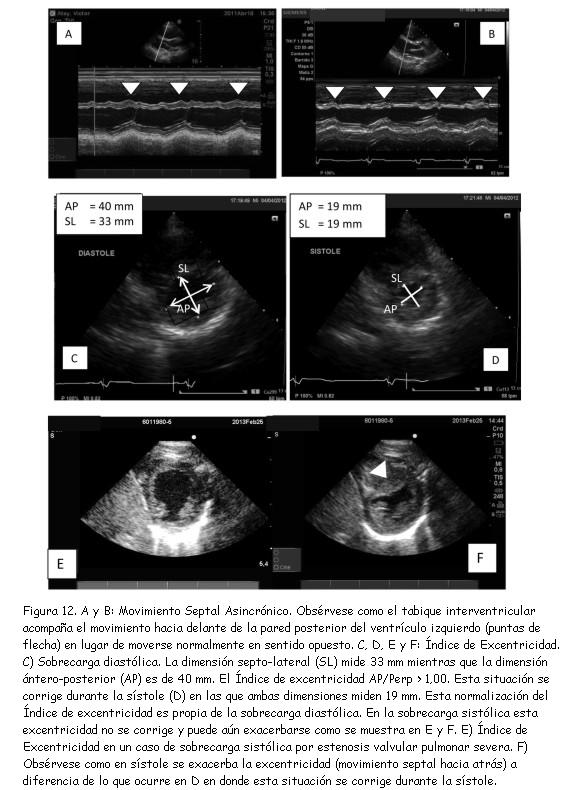

La repercusión de la sobrecarga ventricular derecha sobre la motilidad del septum interventricular constituye un hallazgo conocido. El movimiento septal asincrónico o “paradójico” es expresión de sobrecarga ventricular derecha tanto sistólica como diastólica (figuras 12 A y B).

En condiciones de carga normales, en la proyección parasternal eje corto a nivel de los músculos papilares, el eje ántero-posterior del VI y su perpendicular son iguales entre sí, ya que la cavidad presenta una forma circular tanto en diástole como en sístole. La relación entre estas dos dimensiones se conoce como índice de excentricidad (37,47,48).

Tanto la sobrecarga sistólica como la sobrecarga diastólica del VD alteran el índice de excentricidad. En ambas situaciones, el índice se torna mayor a 1,00, pero con la peculiaridad que en la sobrecarga diastólica esta situación tiende a corregirse en sístole (figura 12 D) mientras que si la sobrecarga es sistólica, esta relación no se modifica o puede exacerbarse durante la sístole (figura 12 E y F). El hallazgo es significativo porque estas distorsiones afectan la función diastólica del VI(47) por la interdependencia que existe entre ambos ventrículos.